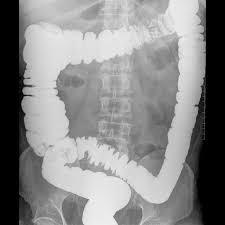

Los tipos especiales de exámenes de rayos X llamados estudios de contraste utilizan tintes con base de yodo o materiales de contraste, como el bario, junto con las radiografías para que los órganos aparezcan en la radiografía y obtener mejores imágenes. Por ejemplo, las radiografías del tracto gastrointestinal inferior, normalmente llamado examen de enema de bario, se emplean para tomar imágenes después de que el intestino se llena con sulfato de bario. Otro estudio, un pielograma intravenoso, usa un colorante especial para examinar la estructura y el funcionamiento del sistema urinario (uréteres, vejiga y riñones).

Radiografías del tracto gastrointestinal inferior (enema de bario): se puede restringir su alimentación durante algunos días antes del estudio. Se usan laxantes, enemas, o ambos, para vaciar el intestino grueso. Para el estudio, usted se acuesta y será sujetado a una mesa. Se toma una serie de radiografías. Luego el líquido de bario se coloca dentro del intestino por medio de un tubo pequeño y blando ubicado en el recto. El líquido se siente frío. Se procede a tomar más imágenes mientras la mesa le inclina a usted en diferentes posiciones. Esto ayuda a que el bario se mueva por los intestinos de modo que puedan verse en las radiografías. Tiene que permanecer acostado inmóvil y contener la respiración cuando se toma cada imagen.

Después del estudio, puede ir al baño para eliminar la solución de bario de los intestinos. (Pueden pasar varios días hasta que esta se haya eliminado por completo. Sus deposiciones pueden ser más secas, más duras y de color claro durante este tiempo).

Para obtener imágenes más claras, por lo general se realiza un examen con “contraste doble”. En este examen se usa una cantidad más pequeña de líquido de bario más espeso. Después que el bario está adentro, se hace ingresar aire en sus intestinos. Esto puede causar una sensación de hinchazón y malestar, junto con la ganas de vaciar los intestinos.